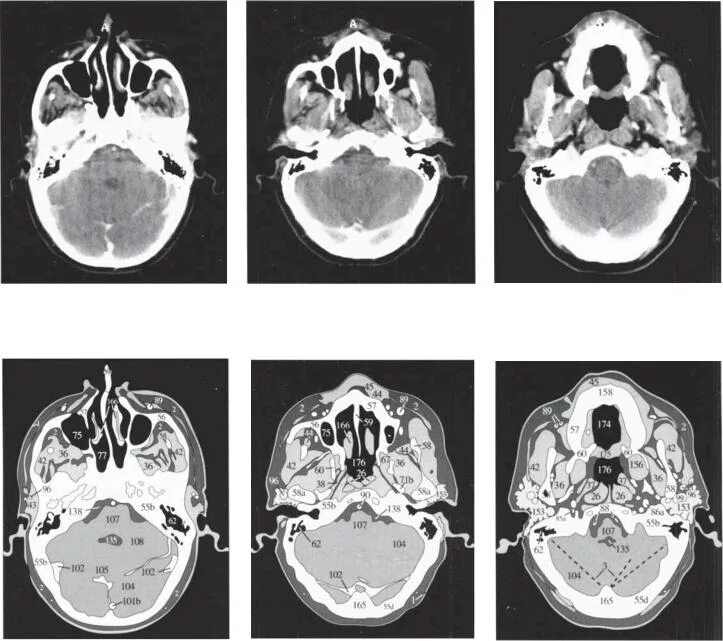

Кт пример